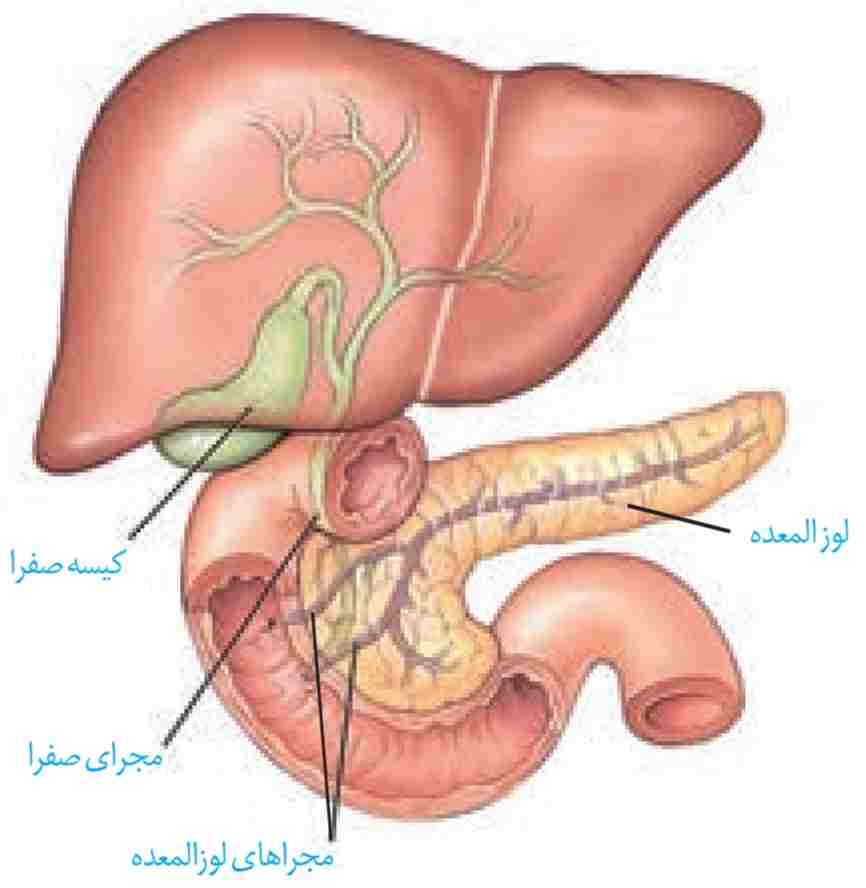

گوارش در رودهٔ باریک: کیموس به تدریج وارد رودهٔ باریک میشود تا مراحل پایانی گوارش به ویژه در دوازدهه انجام شود. صفرا، شیرههای روده و لوزالمعده که به دوازدهه میریزند به کمک حرکات روده، در گوارش نهایی کیموس نقش دارند (شکل ۱۰).

شکل ۱۰- صفرا از راه مجاری صفراوی کبد به یک مجرای مشترک وارد و در کیسه صفرا ذخیره میشود.

شکل ۱۰- صفرا از راه مجاری صفراوی کبد به یک مجرای مشترک وارد و در کیسه صفرا ذخیره میشود.

صفرا: کبد، صفرا را میسازد. صفرا آنزیم ندارد و ترکیبی از نمکهای صفراوی، بیکربنات، کلسترول و فسفولیپید است. صفرا به دوازدهه میریزد و به گوارش چربیها کمک میکند. همچنین بیکربنات صفرا به خنثی کردن حالت اسیدی کیموس معده کمک میکند.

گاهی ترکیبات صفرا در کیسه صفرا رسوب میکنند و سنگ ایجاد میشود. رژیم غذایی پرچرب در ایجاد سنگ کیسهٔ صفرا نقش دارد (شکل ۱۱).

شیرهٔ لوزالمعده: آنزیمها و بیکربنات لوزالمعده به دوازدهه میریزند. لوزالمعده، آنزیمهای لازم برای گوارش شیمیایی انواع مواد را تولید میکند. پروتئازهای لوزالمعده درون رودهٔ باریک فعّال میشوند. بیکربنات اثر اسید معده را خنثی میکند. به این ترتیب دیوارهٔ دوازدهه از اثر اسید حفظ و محیط مناسب برای فعالیت آنزیمهای لوزالمعده فراهم میشود.